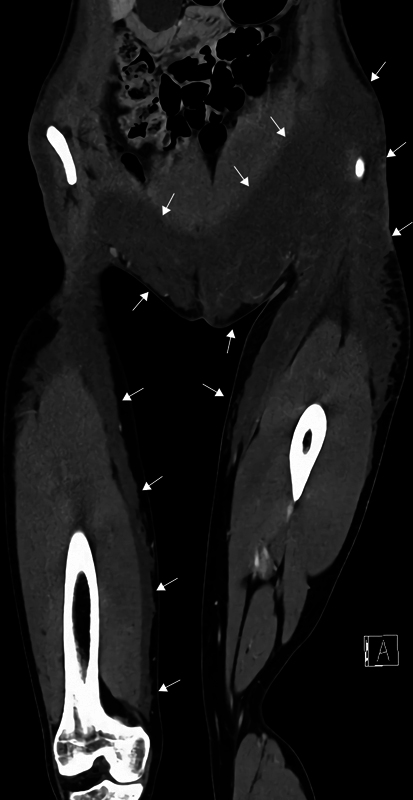

臀部填充注射作为一种整容手术正变得越来越流行,这导致了预期并发症数量的增加,强调了报告已知的、严重的和以前未发现的并发症的重要性,以及它们可能的治疗策略。我们报告了一位18岁的女性,她在注射填充剂进行丰臀手术后出现了严重的长期并发症,包括填充剂移位、感染导致感染性休克和非甲状旁腺高钙血症,这可能导致肾功能不全。到目前为止,我们还没有发现任何描述非甲状旁腺高钙血症与充水之间关系的报告。此外,我们概述了一种涉及微创方法的治疗方案,包括每日冲洗,手动按压和被动抽吸。在随访中,患者恢复了日常生活,除了右大腿内侧有一个实性肿块外,没有持久的后遗症。

Filler injections for buttock augmentation are becoming more popular as a cosmetic procedure, which leads to an expected increase in the number of complications emphasizing the importance of reporting cases with both well-known, severe, and previously undiscovered complications, as well as their possible treatment strategies. We present an 18-year-old woman who suffered severe long-term complications following Aquafilling injections for buttock augmentation, including filler migration, infection leading to septic shock, and nonparathyroid hypercalcemia, which has the potential to cause renal insufficiency. To date, we have not found any reports describing the association between nonparathyroid hypercalcemia and Aquafilling. Additionally, we outline a treatment regimen involving a minimally invasive approach, which includes daily irrigation, manual compression, and passive evacuation. At follow-up, the patient returned to her everyday life with no lasting sequelae, except for a solid mass medially on the right thigh.